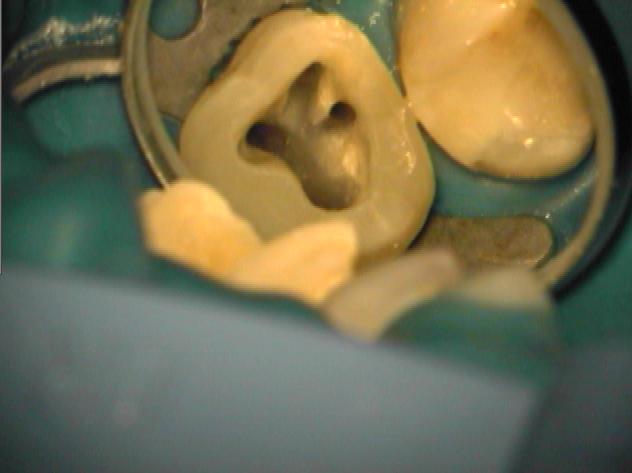

Klinische Situation nach abgeschlossener Aufbereitung

Vergrößerte Situation

Vergrößerte Situation; deutlich sind die 4 Kanaleingänge zu erkennen